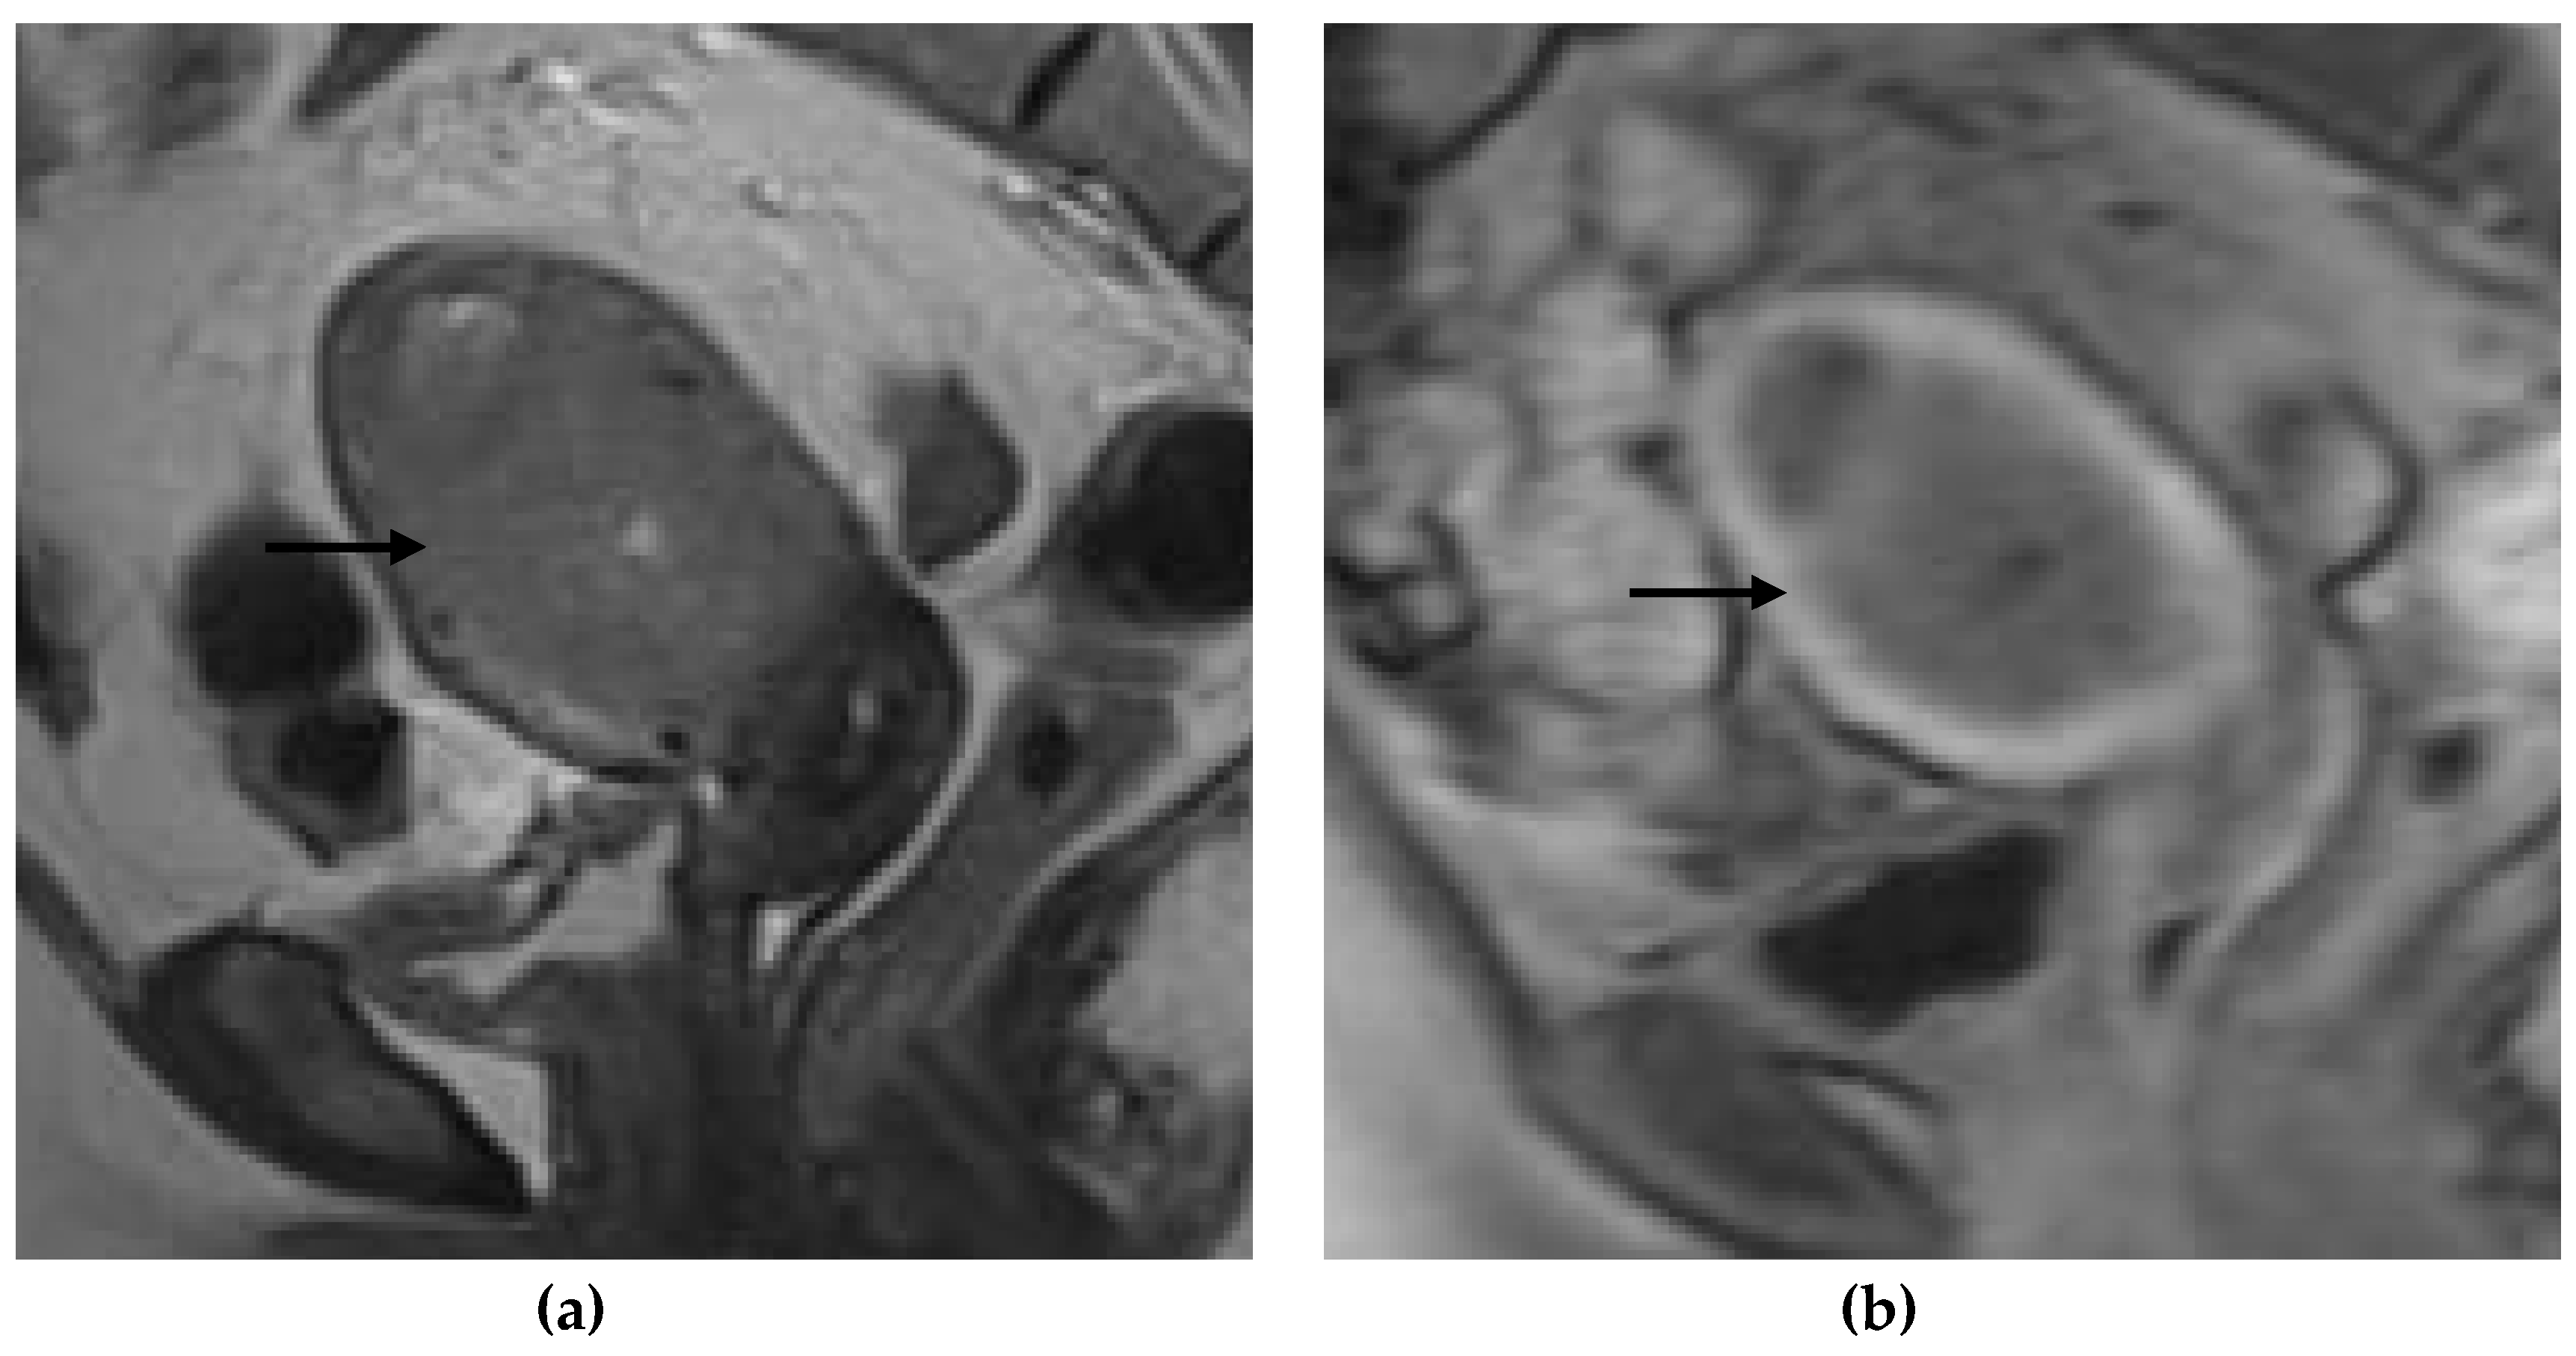

Figure 1, Figure 2, Figure 3 and Figure 4 depict the representative MRI images of tumors with < 50% myometrial invasion and ≥50% myometrial invasion, as well as the representative combined T2WI+DCE-MRI images for false-positive and false-negative cases, respectively. The diagnostic performance of MRI in predicting the depth of myometrial invasion is presented in Table 2 and Table 3. The depth of myometrial invasion (any depth) was correctly determined in 75% (n = 24) and 78% (n = 25) of cases on T2WI and DCE-MRI alone, respectively, whereas the percentage increased to 91% (n = 29) of cases when the T2W images were read together with those obtained by DCE-MRI.

Figure 1. Representative MRI images of endometrial carcinoma with <50% myometrial invasion. (a) Axial T2WI, (b) sagittal T2WI, and (c) sagittal DCE-MRI images during the early acquisition stage. Tumors (arrow) with <50% myometrial invasion presented as iso- to mildly hyperintense on T2WI compared to the myometrium (a,b) with an intact junctional zone. On DCE-MRI, the tumors appeared as hypointense masses compared to the adjacent myometrium with intact subendometrial enhancement (SEE), indicating a tumor that is confined to the endometrium (c). Abbreviations: MRI, magnetic resonance imaging; dynamic contrast-enhanced magnetic resonance imaging (DCE-MRI); T2WI, T2-weighted imaging.